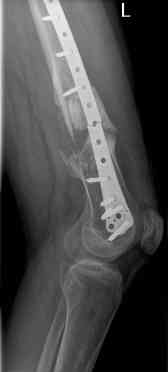

16 yr old boy, high energy motorcycle trauma trauma in July 2005 with:

- hip dislocation + acetabular fracture L

- distal femoral fracture L

- tibial shaft fracture L

- metatarsal fractures L

july 05: LISS femur, LCP plate tibia, double recon. plate post. acetabulum

oct 05: cancellous bone graft femur

aug 06: blade plate + bone graft

nov 06: revision blade plate

feb 07: retrograde nail + bone graft + BMP

may 07: dynamisation nail

sept 07: locking screw removal (max. dynamisation reached)

nov 07: persistant non-union distal femur; other fractures healed uneventfully.

All with gradual/partial weightbearing etc. Currently 50-100% weight bearing, no pain.

Soft tissues are intact. No smoking or diabetes.CRP <2